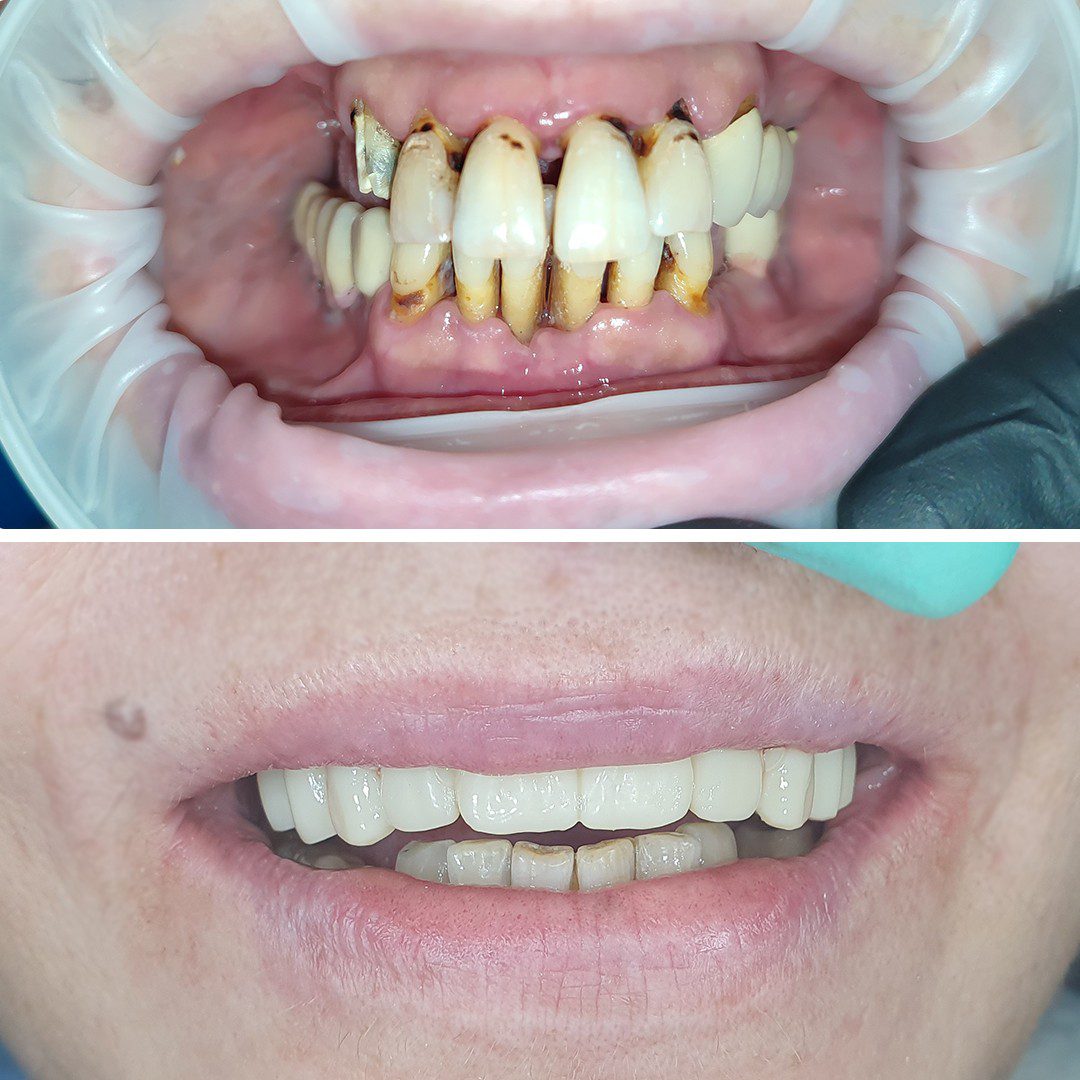

Dinți Ficși în 8-24 de ore pe implanturi dentare cu tehnica All-on-4/All-on-6 este cea mai eficientă și rapidă metodă de restaurare totală a danturii.

Este tratamentul ideal pentru pacienții care își doresc o dantură nouă, fixă și funcțională.

- Aplicare lucrare provizorie pe implanturi

- Lucrarea finală

• Estetică deosebită, asemanatoare dinților naturali

• Stabilitate bună

• Funcționalitate